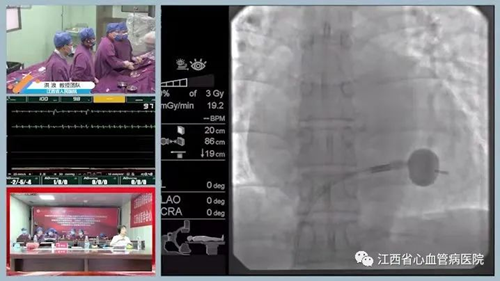

会议期间我院成功开展了二项省内首例新技术:一是CARTO V7 PRIME省内首次正式应用,二是冠脉严重钙化下,shockwave的首次应用。

10:30开始,空中进行多频道线上手术直播,洪浪教授、潘湘斌教授、方哲教授同台开展了二尖瓣缘对缘介入手术,手术顺利完成。

会议当天还进行了经导管主动脉瓣膜置换术、二尖瓣球囊扩张术、结构心脏病手术直播,中部地区冠脉手术直播,腔内影像指导PCI治疗,房颤射频消融及房颤房扑合并脑梗行射频消融术+左心耳封堵术,起搏器手术直播及起搏电极拔除行micra植入的病例汇报,室上速射频消融术等,联袂直播演示了共计25台手术,“云端”展示了我院卓越的介入风采,获得了线上3万余次手术观看点击量。